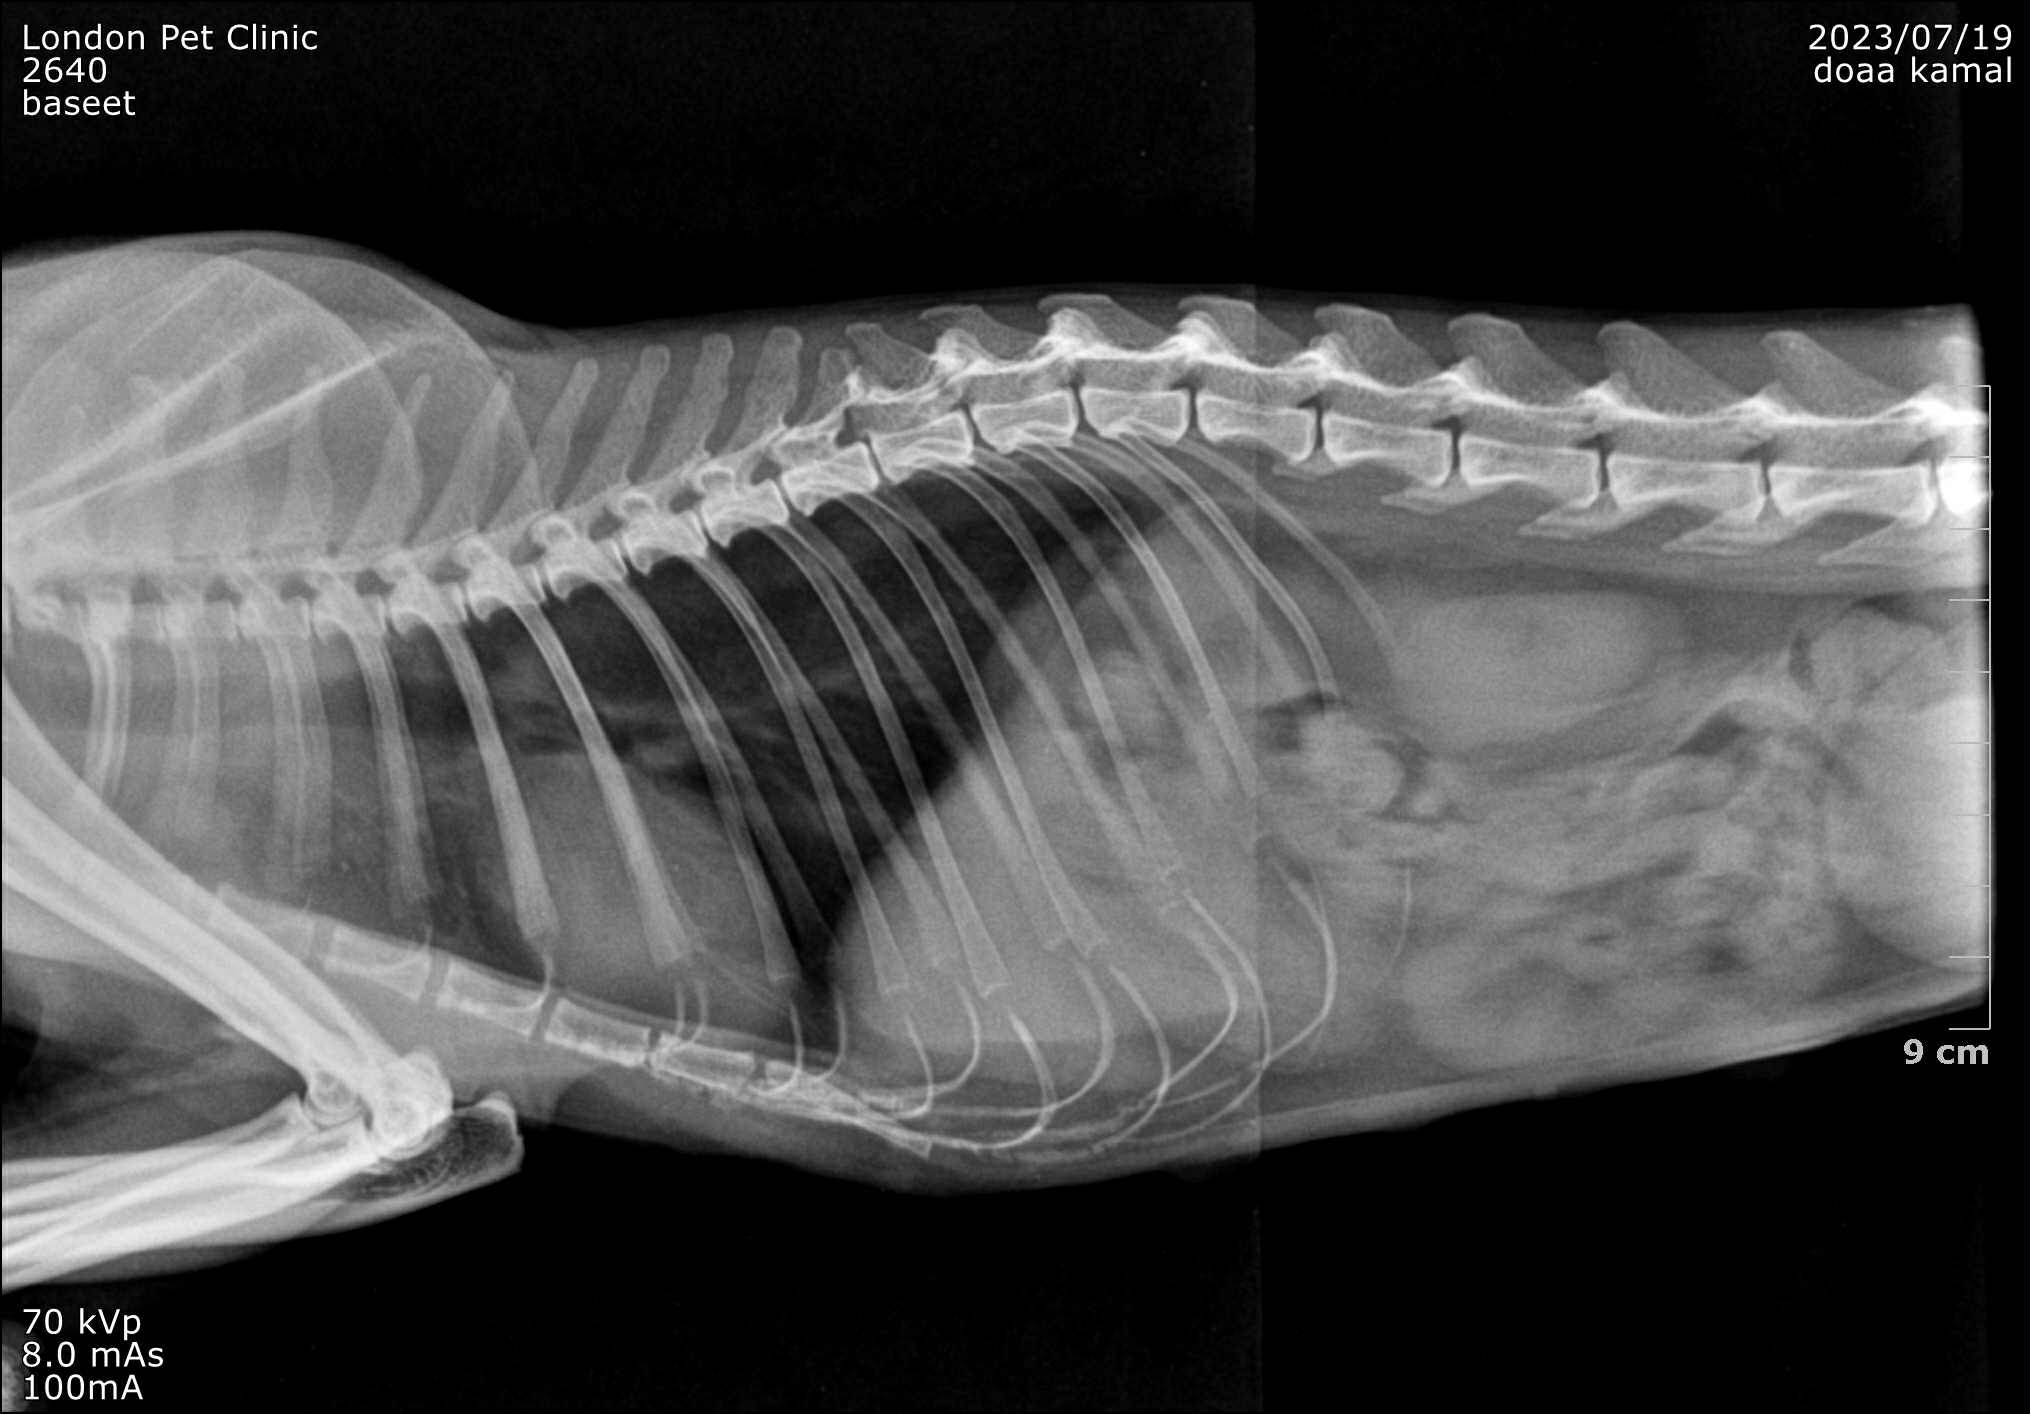

1. X-Rays

• Loss of normal diaphragmatic line

• Loops of gas-filled bowel visible within the thoracic cavity

• Heart silhouette displaced cranially

• Reduced lung fields (atelectasis)

Loss of normal diaphragmatic line -Loops of gas-filled bowel visible within the thoracic cavity